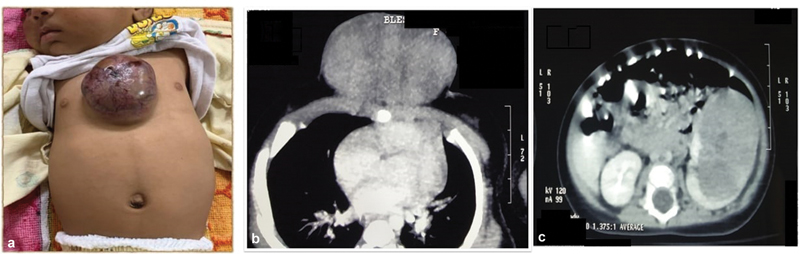

A 4-month-old female child, first in birth order, born by full-term vaginal delivery, and asymptomatic at birth, was referred with a presternal swelling. This had been noticed since the age of 2 months by the parents and was gradually increasing in size. There was no history of loss of appetite or weight. She had normal bowel and bladder habits. There were no complaints other than the presence of the presternal swelling. An ultrasonography (USG) of the swelling done before referral was suggestive of hemangioma or arteriovenous malformation. On examination, a 6 × 4 cm, round, well defined, firm, nontender, noncompressible swelling was present over the presternal area with overlying darkened skin and few areas of ulceration and eschar ([Fig. 1A]). Incidentally, fullness was noted in the left flank region and on abdominal examination, a mass of size 4 × 5 cm was palpable in the left lumbar region that was firm, well defined, smooth, bimanually palpable, and nonballotable. She had no features of any syndrome associated with Wilms' tumor. USG abdomen revealed a hyperechoic 4 × 4 cm left renal mass. Contrast-enhanced computed tomography (CECT) chest showed that the presternal mass had no intrathoracic extension. ([Fig. 1B]). CECT of abdomen showed a 5.1 × 3.8 × 5.3 cm hyperdense exophytic mass arising from the left kidney with no major vessel encasement or calcifications ([Fig. 1C]).

Fig. 1 (A) Single large skin metastasis in lower presternal area at presentation; (B) contrast-enhanced computed tomographic scan of chest shows a 3.8 × 3.8 × 6.3 cm mass in the presternal area lying in subcutaneous plane with no intrathoracic extension; (C) contrast-enhanced computed tomographic scan of abdomen shows a 5.1 × 3.8 × 5.3 cm hyperdense exophytic mass arising from the left kidney with no major vessel encasement or calcifications.